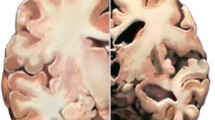

Conventional markers of AD reflect amyloid and tau pathology, as the core neuropathological elements of the disease [6]. The histological features of abnormal accumulation of these two proteins, amyloid plaques and neurofibrillary tangles, have been first observed and described at the same time as the clinical symptoms of the disease itself [7]. However, the field has recently shifted its focus towards methods and markers that might reveal AD-associated disturbances in brain function rather than simply in structure. This was motivated by numerous studies that have shown that synaptic dysfunction and loss such as decreased synaptic density in neocortex and limbic regions, seem to be an early event in AD, present already in the pre-dementia (MCI) stage of the disease [8,9,10,11]. Moreover, assembly of amyloid β protein (Aβ) into oligomers, presumably the most toxic amyloid species in the brain, during the AD pathophysiological process has been shown to disrupt synaptic function and structure, deplete synaptic number and consequently impair memory [12, 13]. In addition to the direct deleterious effect on synapses, recent findings provide evidence that Aβ oligomers have the potential to indirectly impair synaptic and neuronal activity by inducing AD-associated tau pathology, neuritic degeneration and neuroinflammation [12, 14,15,16]. Altogether, synaptic loss, being more extensive than neuronal loss when analyzed in the same brain regions, has been shown to be the best neuropathological correlate of cognitive impairment in patients along the AD continuum [8, 11, 17, 18].

Some of the first attempts to directly assess topographical correlates of EEG-recorded brain activity included the dipole source localization method. It involved “fitting” of a single dipole in the three-dimensional (3-D) coordinating system that depicts the corresponding center of gravity and strength of the intracerebral activity [98]. Using the referenced technique, several studies have shown more anteriorly located centers of gravity of alpha and beta activity in AD patients compared with healthy controls and MCI subjects. The general anteriorization of fast-frequency activity was hypothesized to be associated with the early and more severe neuropathology in the posterior brain areas in patients along the AD continuum. In addition, the degree of shift was reported to be sensitive to disease activity and progression, as it correlated with the severity of cognitive impairment and was predictive of the development of AD in MCI patients [31, 37, 69]. Dipole source localization is a simple and user-friendly estimator of the electric gravity center, but does not portray a realistic location of the EEG generators, for two reasons: it calculates a single locus of activity, while the exact number of dipoles to be optimally fitted remains unknown [19].

Mapping the electrical generators in the brain that give rise to the electric field topographies at the level of the scalp is enabled by mathematical calculations of the EEG inverse solution. Low-resolution electromagnetic tomography (LORETA) is a functional neuroimaging method that estimates cortical sources of brain electrical activity in a 3-D human head model (Fig. 1) [99]. Decreased activity in parieto-occipital alpha sources and widespread increases in activity in delta and theta bands have been repeatedly reported in AD patients compared with healthy controls [51, 72, 73, 78, 80, 89]. Babiloni et al. showed that some of the referred disturbances in cortical EEG rhythms occur already in subjects with memory complaints (SMC) and MCI patients, supporting the hypothesis of brain functional disturbances already in the pre-dementia stages of the disease [74]. In addition, introduced studies have shown that cortical sources of delta, theta and alpha activity correlate with neuropsychological test scores and are sensitive to disease progression, suggesting clinical implication for EEG-based imaging techniques in cognitively impaired individuals [51, 72, 73, 75, 80]. The LORETA method can also be utilized for regional assessment of brain functional connectivity. Canuet et al. reported decreased lagged phase synchronization between the medial frontal/parietal region and the left temporal and bilateral inferior parietal cortex in the alpha 2 frequency band and the most prominent increase in synchronization of low-frequency activity of the temporal lobe in 125 AD patients [78]. EEG neuroimaging methods can therefore be used for topographical investigation of resting-state disruptions of cortical activity and functional connectivity in AD patients.